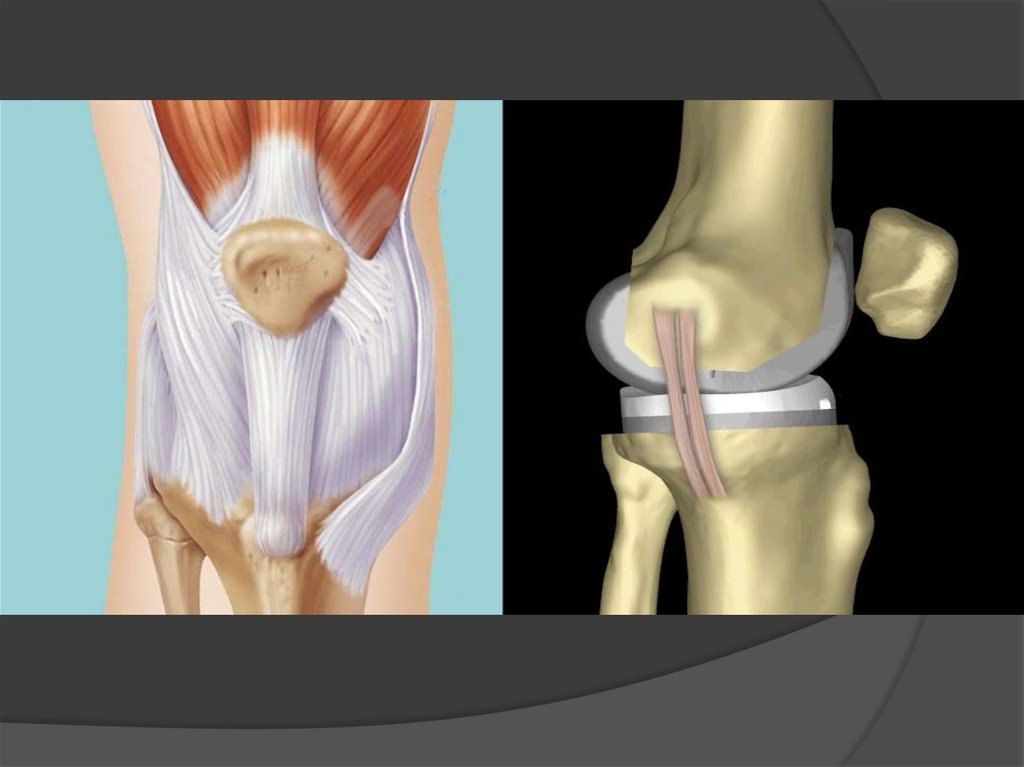

Надколінок - patella

Губчаста сесамоподібна кістка, розміщена у товщі чотириголового

м’яза стегна, обернена гострим кінцем (верхівкою) вниз і має:

- основу надколінка – basis patellae;

- верхівку надколінка – apex patellae;

- передню поверхню – facies anterior;

- суглобову поверхню – facies articularis.